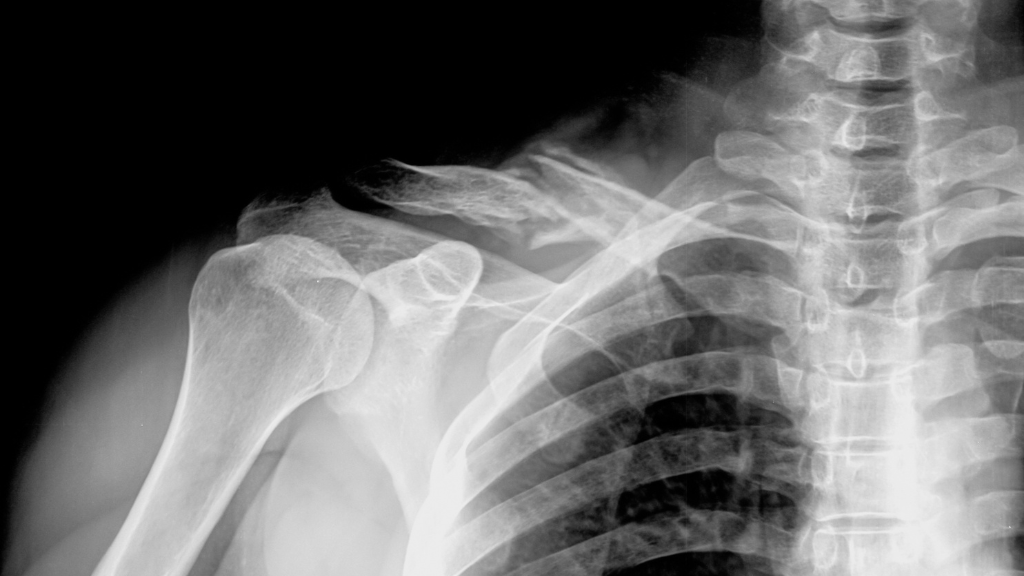

Kalsium on välttämätöntä vahvoille luille. Kun saat liikaa fosforia ja liian vähän kalsiumia, se voi johtaa luukatoon. Pitkällä aikavälillä tämä lisää osaltaan riskiä osteoporoosin ja luunmurtumien kehittymiselle. Erityisesti ne, jotka juovat virvoitusjuomia päivittäin, ovat alttiimpia näille haittavaikutuksille.

Kehostamme on oltava tarkka tasapaino kalsiumin ja fosforin välillä. Jos tämä tasapaino järkkyy, keho ottaa kalsiumia luista palauttaakseen tasapainon. Tämä saattaa vaikuttaa harmittomalta, mutta pitkällä aikavälillä se heikentää luitasi huomattavasti.

Useat tutkimukset ovat osoittaneet, että ihmisillä, jotka juovat paljon virvoitusjuomia, on heikommat luut kuin niillä, jotka eivät juo. Erityisesti naisilla on suurempi riski osteoporoosiin, kun he juovat säännöllisesti kolaa tai muita hiilihapotettuja juomia.

Vaikka lasillinen silloin tällöin ei olekaan katastrofi, tutkimukset osoittavat, että päivittäinen virvoitusjuomien juominen kasvattaa merkittävästi luuongelmien riskiä myöhemmin elämässä. Ei ole liioiteltua sanoa, että virvoitusjuoma saattaa olla hiipivä uhka terveydellesi.

Luusi ovat kehosi perusta, ja kalsiumin puute tai liiallinen fosforin saanti voi aiheuttaa peruuttamatonta vahinkoa. Jos haluat estää osteoporoosin kehittymisen vanhempana, on järkevää ryhtyä toimiin nyt.